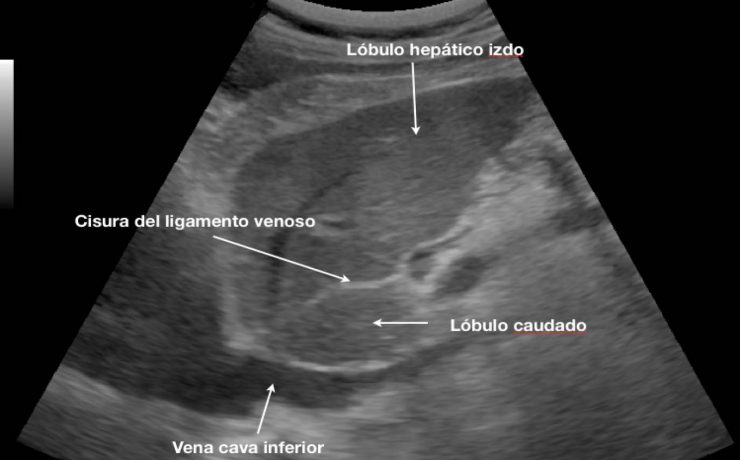

La equinococosis alveolar es causado por el metacestodo Equinococcus multilocularis, en los humanos proliferan en el hígado, induciendo un crecimiento lento progresivo semejante a un tumor. La infección ocurre en todos los continentes, cursa como una infección crónica con estado latente e incluso más de un tercio con detectados incidentalmente,